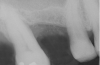

Once it is determined that the twist drill (2.1-mm diameter) is within 1 mm of the sinus floor, the second drill (2.8-mm diameter) and third drill (3.5-mm diameter), if desired, are used to penetrate to within 1 mm of the sinus floor (Figure 3). The amount of osteotomy widening is dependent upon tactilely perceived bone quality.

Figure 3  The osteotomy was completed with the 2.1-, 2.8-, and 3.5-mm twist drills without penetrating into the sinus.

Figure 3